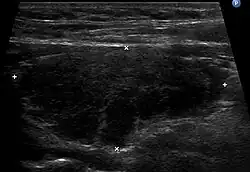

Do charakterystycznych cech choroby należą limfocytowe (limfocyty T, działające destrukcyjnie na miąższ gruczołu tarczowego[5]) nacieki w obrębie tarczycy[12][27][5][2] (obraz w badaniu USG bywa określany jako tarczyca „wygryziona przez mole”, typowo w opisie stwierdza się bardzo niejednorodną, obniżoną, echogeniczność, nacieki podścieliska i wzmożone unaczynienie[40]), obecność (limfocyty B aktywowane przez limfocyty T podlegają przekształcaniu w plazmocyty i produkują przeciwciała[5]) przeciwciał przeciwko tyreoglobulinie (anty-TG; TgAb, anti-thyroglobulin antibody) oraz tyreoperoksydazie (anty-TPO; TPOAb, anti-thyroid peroxidase antibodies) w surowicy[2][12][3]. W obrębie gruczołu tworzą się pęcherzyki limfoidalne z centrami rozrodczymi. Miąższ ulega zwłóknieniu i zanikowi[27]. Apoptotyczne zniszczenie komórek tarczycy powoduje upośledzenie syntezy hormonów[41]. W gruczole obecne są duże komórki pęcherzykowe z obfitą ziarnistą cytoplazmą kwasochłonną (komórki Hürthla, komórki Askanazy'ego, komórki oksyfilne)[27]. Odnotowywane są także okresowe zaburzenia hormonalne[2][12][3]. Gruczoł tarczowy jest blady, o konsystencji od gumowatej do twardej[27]. Chorobie może towarzyszyć zarówno eutyreoza, jak i niedoczynność lub nadczynność gruczołu tarczowego[2]. Nadczynność tarczycy w przebiegu przewlekłego zapalenia tego gruczołu, występuje w przejściowej, krótkotrwałej formie w początkowym okresie choroby i jest wynikiem wydostawania się z uszkodzonych przez proces zapalny pęcherzyków tarczycy nadmiernej ilości utworzonych wcześniej hormonów[2][12][3].

W badaniu ultrasonograficznym przeprowadzonym we wczesnej fazie choroby tarczyca może być jedynie powiększona, bez typowej obniżonej echogeniczności[3].